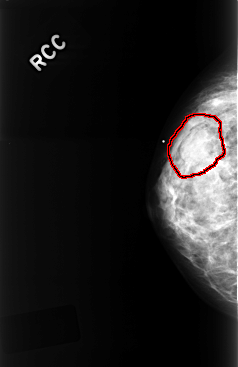

C_0327_1.RIGHT_CC

RIGHT_CC LINES 4400 PIXELS_PER_LINE 2856 BITS_PER_PIXEL 12 RESOLUTION 50 OVERLAY

FILE: C_0327_1.RIGHT_CC.OVERLAY

TOTAL_ABNORMALITIES 1

ABNORMALITY 1

LESION_TYPE MASS SHAPE OVAL MARGINS OBSCURED

ASSESSMENT 3

SUBTLETY 4

PATHOLOGY BENIGN

TOTAL_OUTLINES 1

BOUNDARY